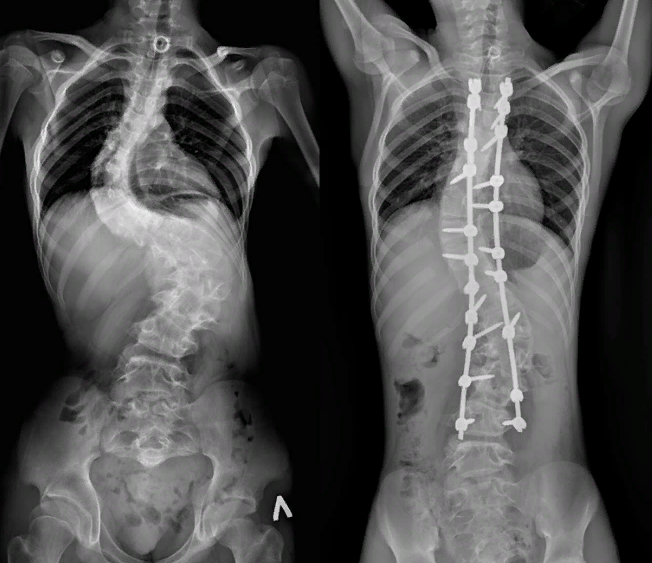

Результат операции радует

Второй скачок роста, произошедший у Мурата в период его воспитания, еще больше усилил деформацию позвоночника, причем во всем, особенно в грудном и поясничном отделах. Это затрудняло передвижение и в совокупности с другими проблемами негативно сказывалось на качестве жизни. Врачи знали о необычайной сложности операции.

Предстояло решить много проблем, так что рассчитывать на быстрое завершение не приходилось. В течение 7 часов хирурги исправили сильнейшее искривление. В связи с высокой степенью деформации позвоночника возникла необходимость удаления костных структур и 3-х ребер. Врачи установили специально разработанную металлическую конструкцию. Благодаря костному аутотрансплантату из резецированных позвонков вокруг стержня начнет формироваться костный блок. Он также укрепляет и стабилизирует имплантированные металлические элементы.

Мурат быстро пришел в себя и уже выздоровел. Врачи дают положительный послеоперационный прогноз и уверяют, что теперь он сможет свободно передвигаться, начать заниматься спортом и даже кататься на велосипеде. Правильное положение позвоночника, обеспеченное надежной конструкцией, защитит внутренние органы от деформации и снижения функциональности.